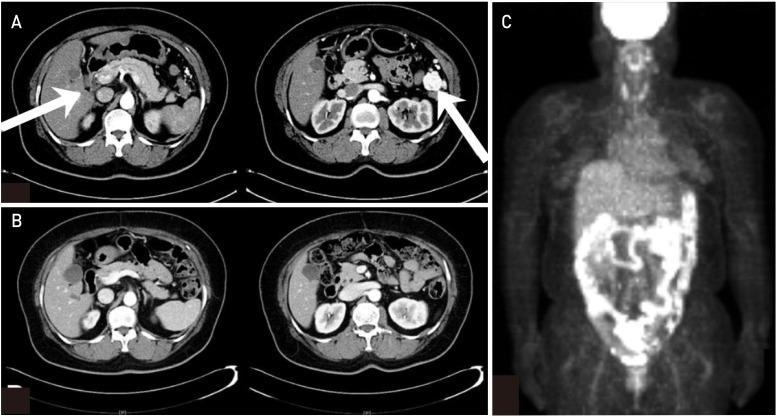

Steroid cell tumors, not otherwise specified, are infrequently encountered ovarian neoplasms, which constitute <0.1% of all ovarian tumors. Most of these tumors are unilateral, and almost one-third of all cases are reportedly malignant. However, because most of these tumors are diagnosed in the early stage, and do not recur or metastasize, little is known about their response to therapies such as chemotherapy or radiation. Here, we present a rare case of recurrent steroid cell tumor, not otherwise specified that showed a complete response after debulking surgery, radiofrequency ablation, and adjuvant chemotherapy.

未另行指定的类固醇细胞瘤是罕见的卵巢肿瘤,占所有卵巢肿瘤的比例不到0.1%。这些肿瘤大多为单侧性,据报道,所有病例中近三分之一为恶性。然而,由于这些肿瘤大多在早期被诊断出来,且不复发或转移,因此对其对化疗或放疗等治疗的反应了解甚少。在此,我们报告一例罕见的复发性未另行指定的类固醇细胞瘤病例,该病例在肿瘤减灭术、射频消融和辅助化疗后显示出完全缓解。